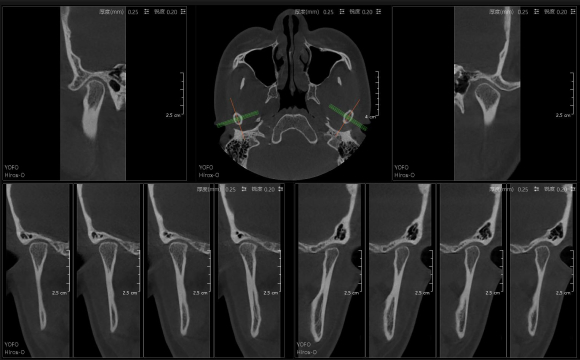

• 3D TMJ视图

3D TMJ视图